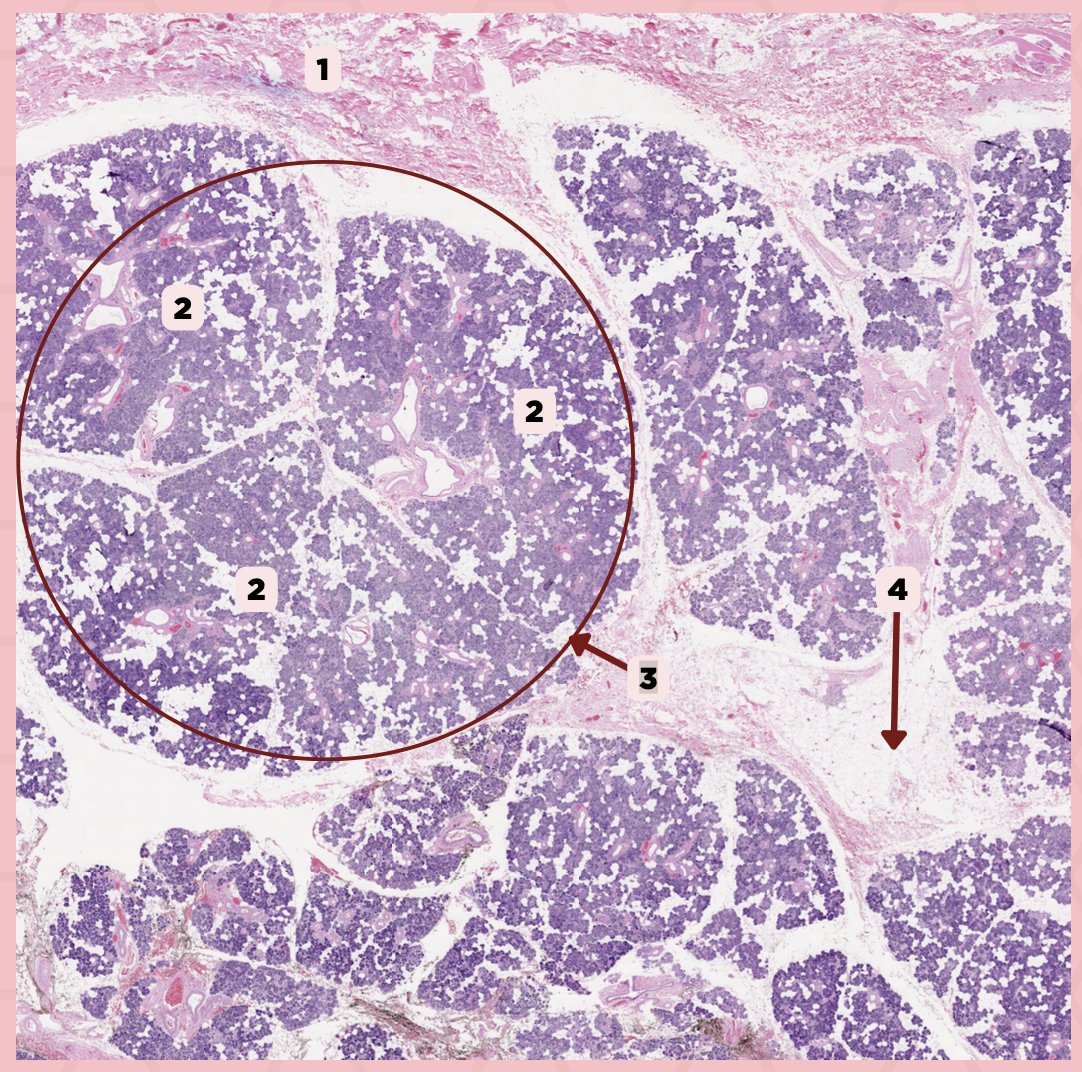

C) Septa

Which of the following structures shown delineate the lobes and lobules of the parotid gland?

A) Capsule

B) Lobule

C) Septa

D) Lymph Nodes

A) Capsule

Which of the following structures encapsulates the parotid gland?

A) Capsule

B) Lobule

C) Septa

D) Lymph Nodes

Parotid

Identify the specimen.

Capsule

Identify the structure labeled as 1.

Septa

Identify the structure labeled as 2.

Lobule

Identify the structure labeled as 3.

Lymph Node

Identify the structure labeled as 4.